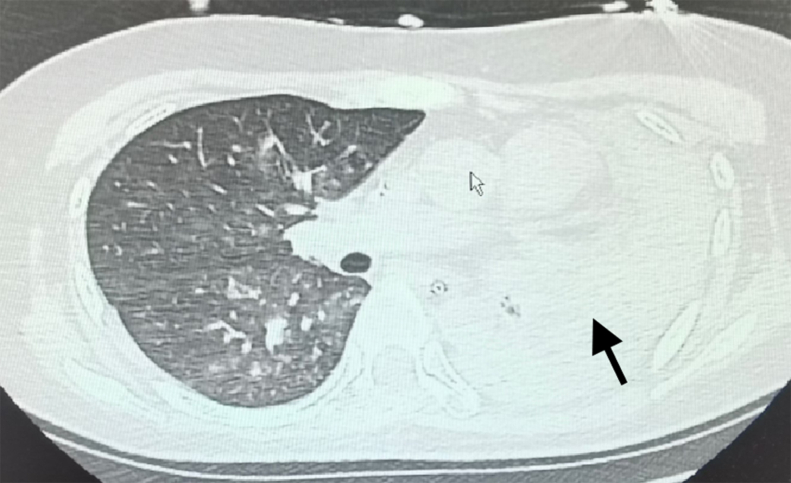

A Boy With Dyspnea.

一个呼吸困难的男孩。